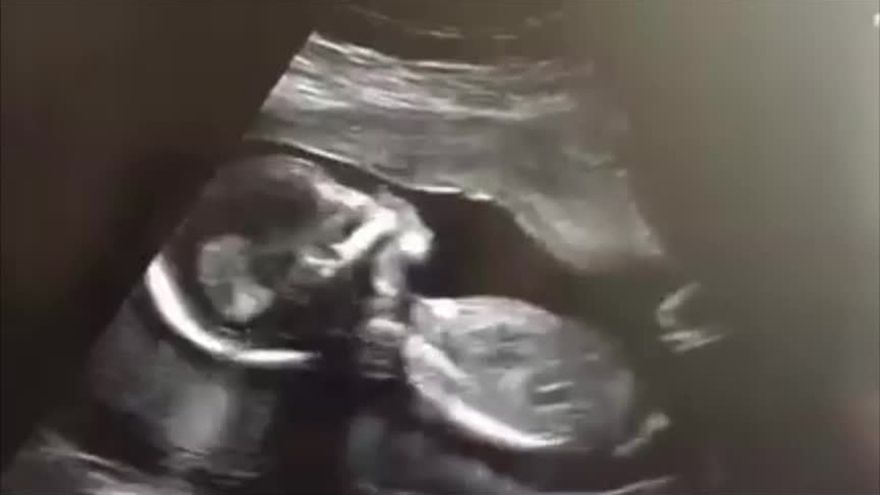

En la jornada que se efectuó en coordinación de Salud Sexual y Reproductiva de la Región de Salud de Panamá Oeste, se atendieron 10 pacientes embarazadas y 3 atenciones de Ultrasonidos ginecológicos, que permitieron proveer más información sobre su embarazo. / Foto/Archivo

En la jornada que se efectuó en coordinación de Salud Sexual y Reproductiva de la Región de Salud de Panamá Oeste, se atendieron 10 pacientes embarazadas y 3 atenciones de Ultrasonidos ginecológicos, que permitieron proveer más información sobre su embarazo.